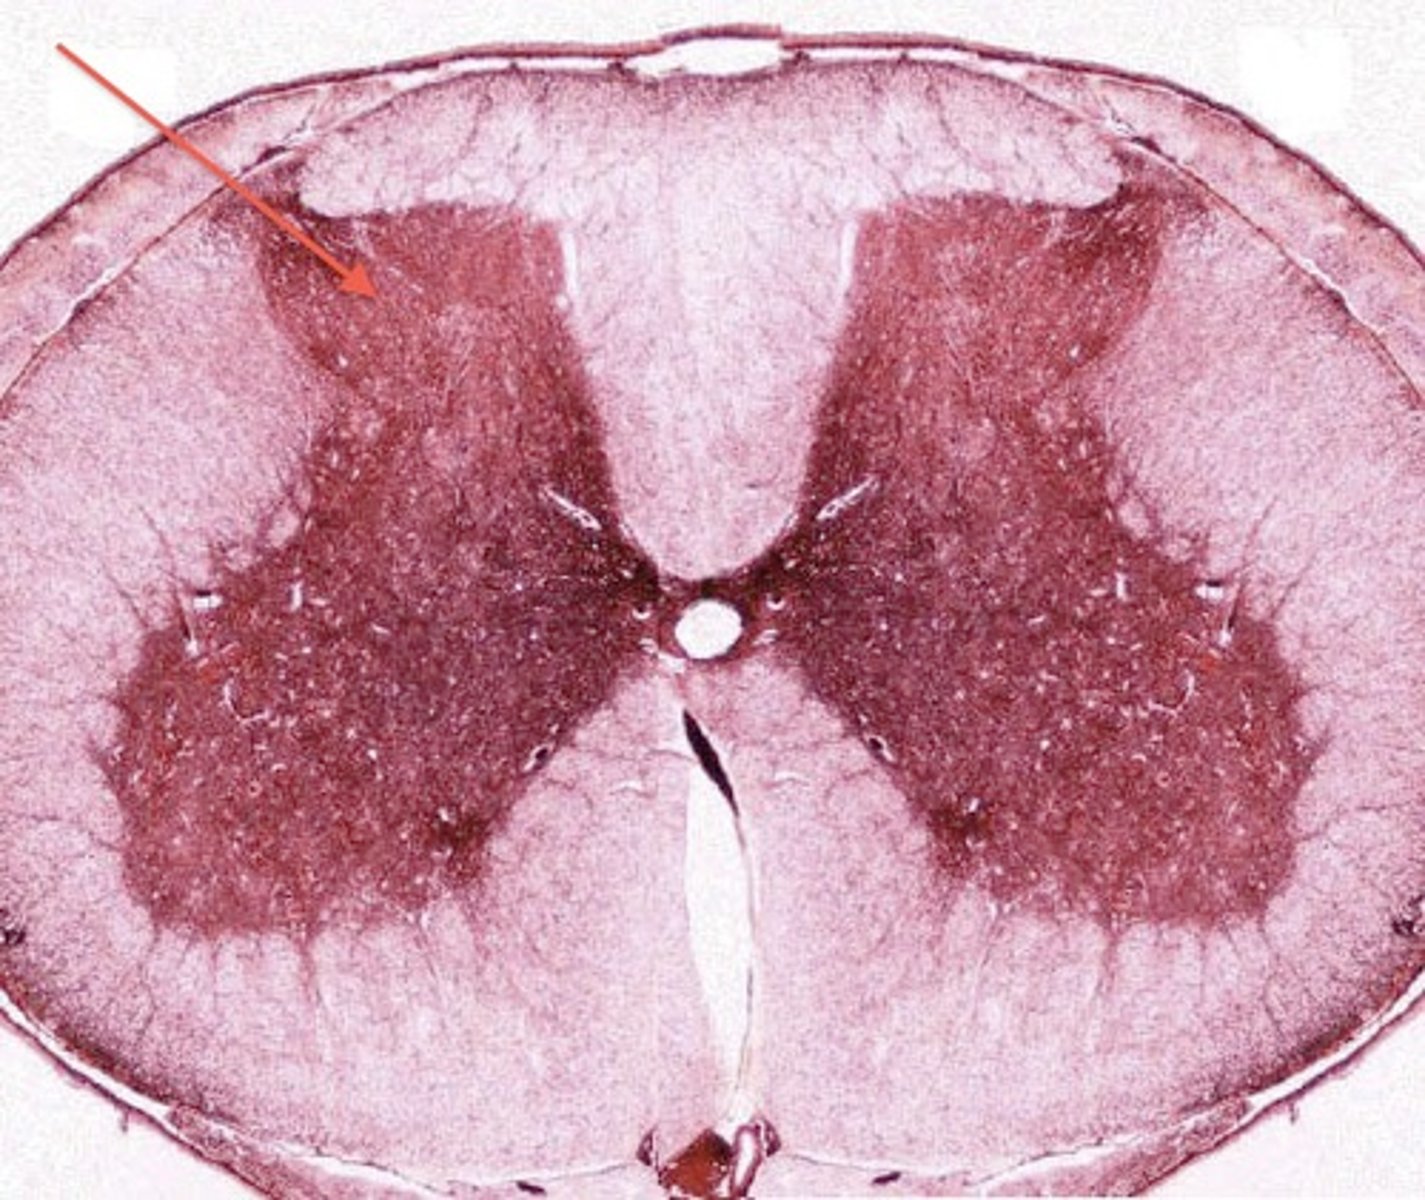

Posterior Gray Horn (microscope slide spinal cord)

Anterior White Column

Posterior White Column (microscope slide spinal cord)

Motor Neurons (microscope slide spinal cord)

Blue Arrow

Central Canal

Anterior Median Fissure

Posterior Median Sulcus